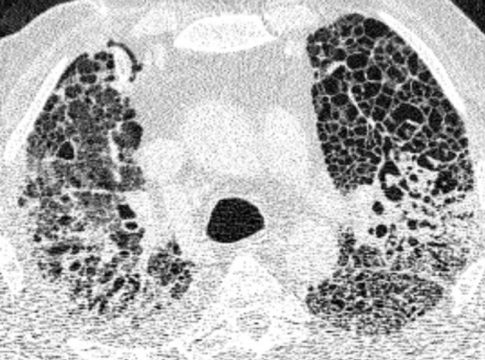

En los pacientes con COVID-19 grave, el daño a los pulmones es tan severo que el cuerpo ya no puede absorber suficiente oxígeno del aire. Los expertos denominan a esta situación "síndrome de dificultad respiratoria aguda" (SDRA).

Los investigadores consideraron una serie de posibles causas de esta insuficiencia pulmonar prolongada, entre ellas un tipo particular de SDRA que provoca una cicatrización pulmonar que da lugar a un engrosamiento y rigidez del tejido. Este tipo de remodelación tisular (conocida como fibrosis) se había observado en algunos pacientes en una fase relativamente temprana de la pandemia.

Este consorcio de investigación interdisciplinar, que reunió a investigadores de toda Alemania, ha confirmado ahora que la insuficiencia pulmonar grave relacionada con el COVID-19 se asocia con frecuencia a una extensa cicatrización de los pulmones.